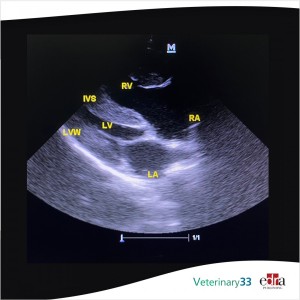

The objective of this study was to establish reference intervals in healthy guinea pigs and to calculate optimal cut-off values for several M-Mode parameters to diagnose dilated cardiomyopathy (DCM)...